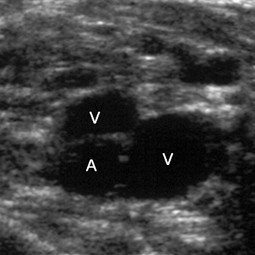

Abb. 3